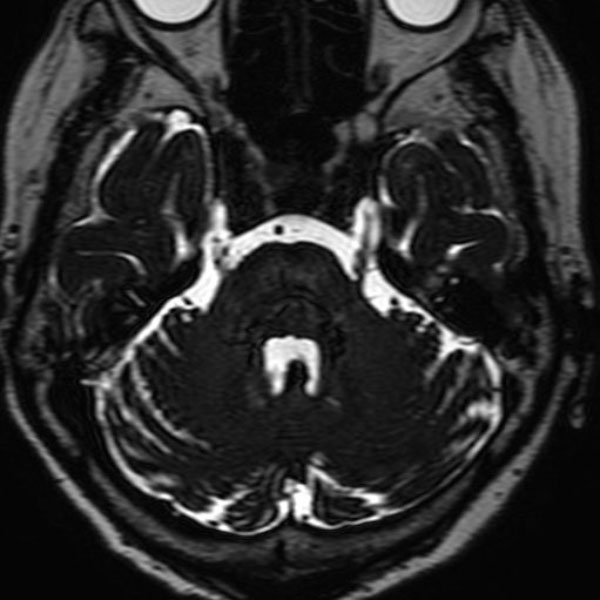

手術前

(MR1)